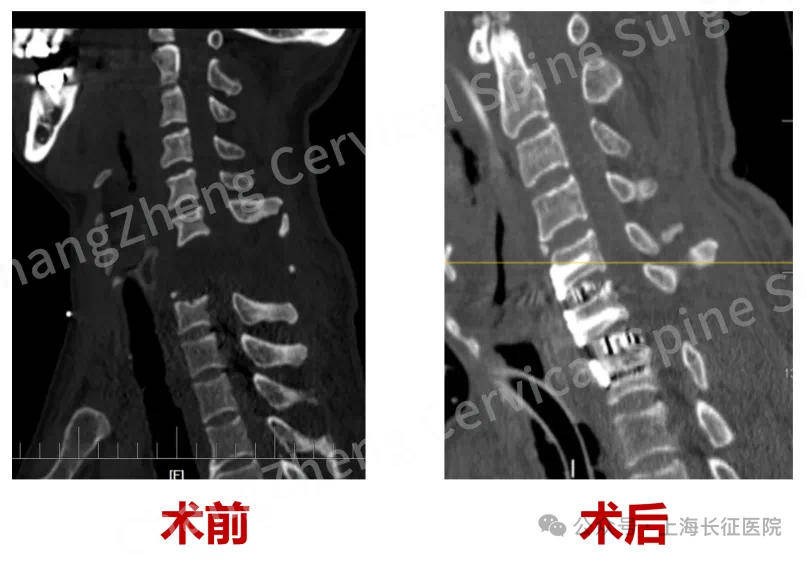

据了解,“身首离断”式的颈椎大跨度脱位本就罕见,成功复位更是闻所未闻。术前影像学检查显示,患者脊髓严重挫伤、关键的神经血管结构撕裂。

▲术前、术后影像对比 图据医院